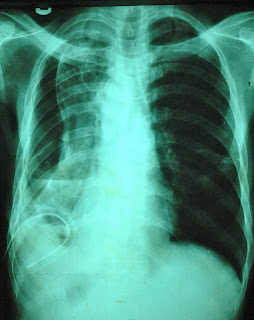

WHAT IS THE DIAGNOSIS?

This X-ray is from a young man with a large pleural effusion which was drained with a chest tube. Most of the fluid is gone but the lung is still unexpanded and the mediastinum is shifted to the right due to volume loss. He has a trapped lung.